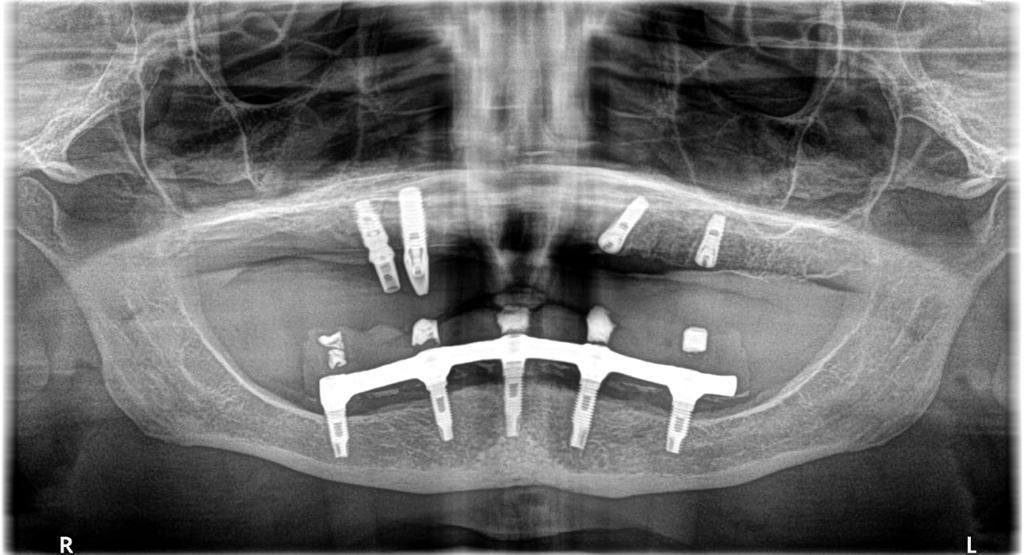

me envían este caso de implante de nuestro amigo Jesus Santillana. Los mas distales que implantes son??? 💁🏻♂️😊

¿Podrían facilitar unas periapicales? Porque los interiores están claros, son hexágono externo, pero los otros se ven bastante mal en la pano.

El hexágono yo no me atrevo a decir nada, el otro, el mesial, parece un tissue level. Sigo queriendo esas periapicales.